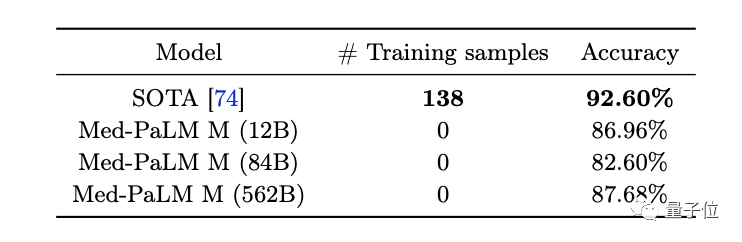

(3)零样本思维链推理能力涌现。Med-PaLM M可以通过胸部X射线图像检测没有训练过的结核病,与针对该类数据集进行专门优化过的SOTA结果相比,它的准确率已相差不大。

不过,它给出的具体报告还是存在具体错误,说明还有不足。